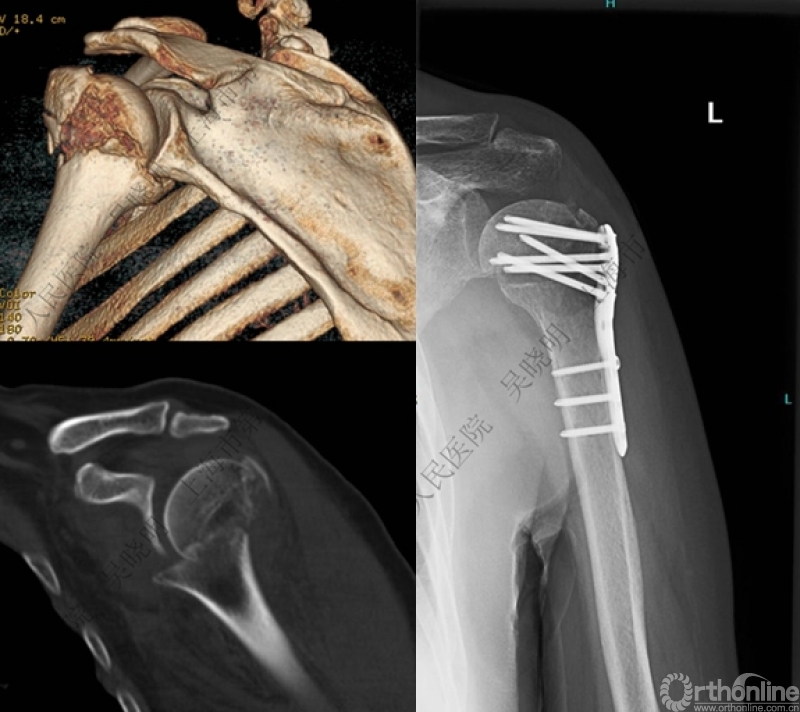

特别警惕伴肱骨头外翻合并大结节骨折的肩关节脱位

警惕:有无肱骨头外翻

伴大结节骨折的老年性肩关节前脱位伴肱骨头外翻

肩关节前脱位合并大结节骨折&肱骨头外翻:外翻压缩型(Neer 分型)

对这型骨折进行手法复位会导致肱骨头和肱骨干之间的连续性消失。肱骨头和肱骨干之间连续性尚存,肱骨头前脱位(Robsion 3b)

警惕孤立性向下移位的大结节骨折

外翻压缩型肱骨近端骨折

钢板固定

X线是孤立性向下移位的大结节,一定要小心,多伴有肱骨外科颈骨折

全麻下闭合复位,钢板固定